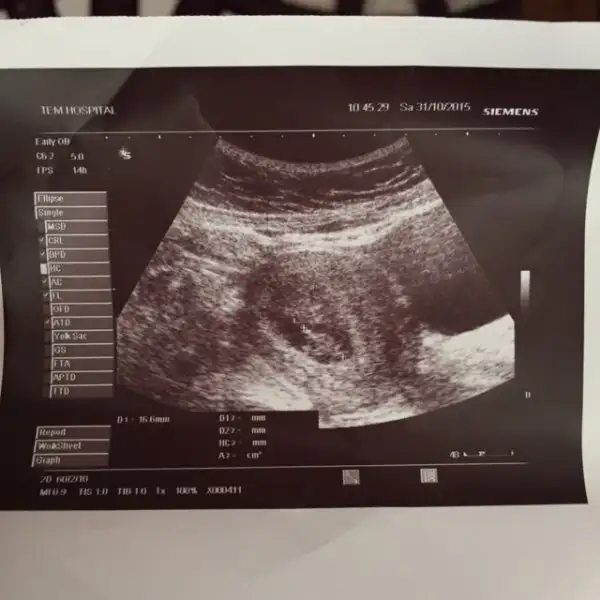

kızlar buda benim 9+3 teki bebişim kısmetse 21 inde 12+3 olacağız 2 li testimiz olucak sizler 11 haftadada gitmişsiniz ne güzel bana 12 haftadan önce gelme dedi doktorum son 1 haftam nasıl geçiçecek bilmiyorum :) umarım bende cinsiyeti öğrenirim. temmuzda bir düşükten sonra Rabbimin bana nasip ettiği 2nci mucizem .İnşallah hepimiz bebişlerimizi sağssalim kucağımıza alırız arkadaşlar....

• IMG_2337.webp

16,7 KB · Görüntüleme: 125